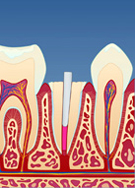

Dersom rotfyllingen vurderes og finnes tett og av god kvalitet, fjernes en del av rotfyllingsmassen for å gjøre plass til stiften (fig. II). Deretter kan stiften festes med en egnet sement (fig. III). Rundt stiften bygger man så opp en masse (konus) som slipes og formes til (fig. IV). Nå kan man ta avtrykk av den beslipte tannen, sende dette til en tanntekniker og få den ferdige kronen tilbake klar for sementering (fig. V og VI). Hele prosessen tar vanligvis 1 til 2 uker.

| figur II | | figur III | | figur IV | | figur V | | figur VI |